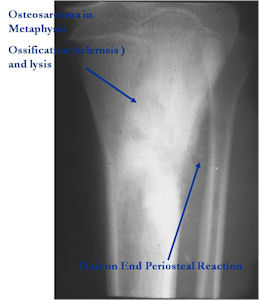

Radiographic Presentation

Plain X-rays:

- Geographic, circumscribed lesion usually around 5cm in size.

- There may be expansion of bone, cortical thinning and cortical breakthrough. A soft tissue mass may accompany this lesion but the soft tissue component is usually contained by the periosteum.

- The periosteum remains intact around the soft tissue component. Might need a CT scan to detect the subtle calcification (Egg Shell Rim of Calcification) associated with an intact periosteal reaction

- The lesion may be entirely radiolucent but usually shows some degree of mineralization. Mineralization may appear stippled like cartilage but do not see chondroid pathologically. Mineralization is sometimes better detected on a CT scan rather than an x-ray.

- Usually less surrounding sclerosis than an osteoid osteoma.

- Arise from the Diaphysis (75%) more commonly than Metaphyseal (25%)

- 4 cm to 6 cm in size